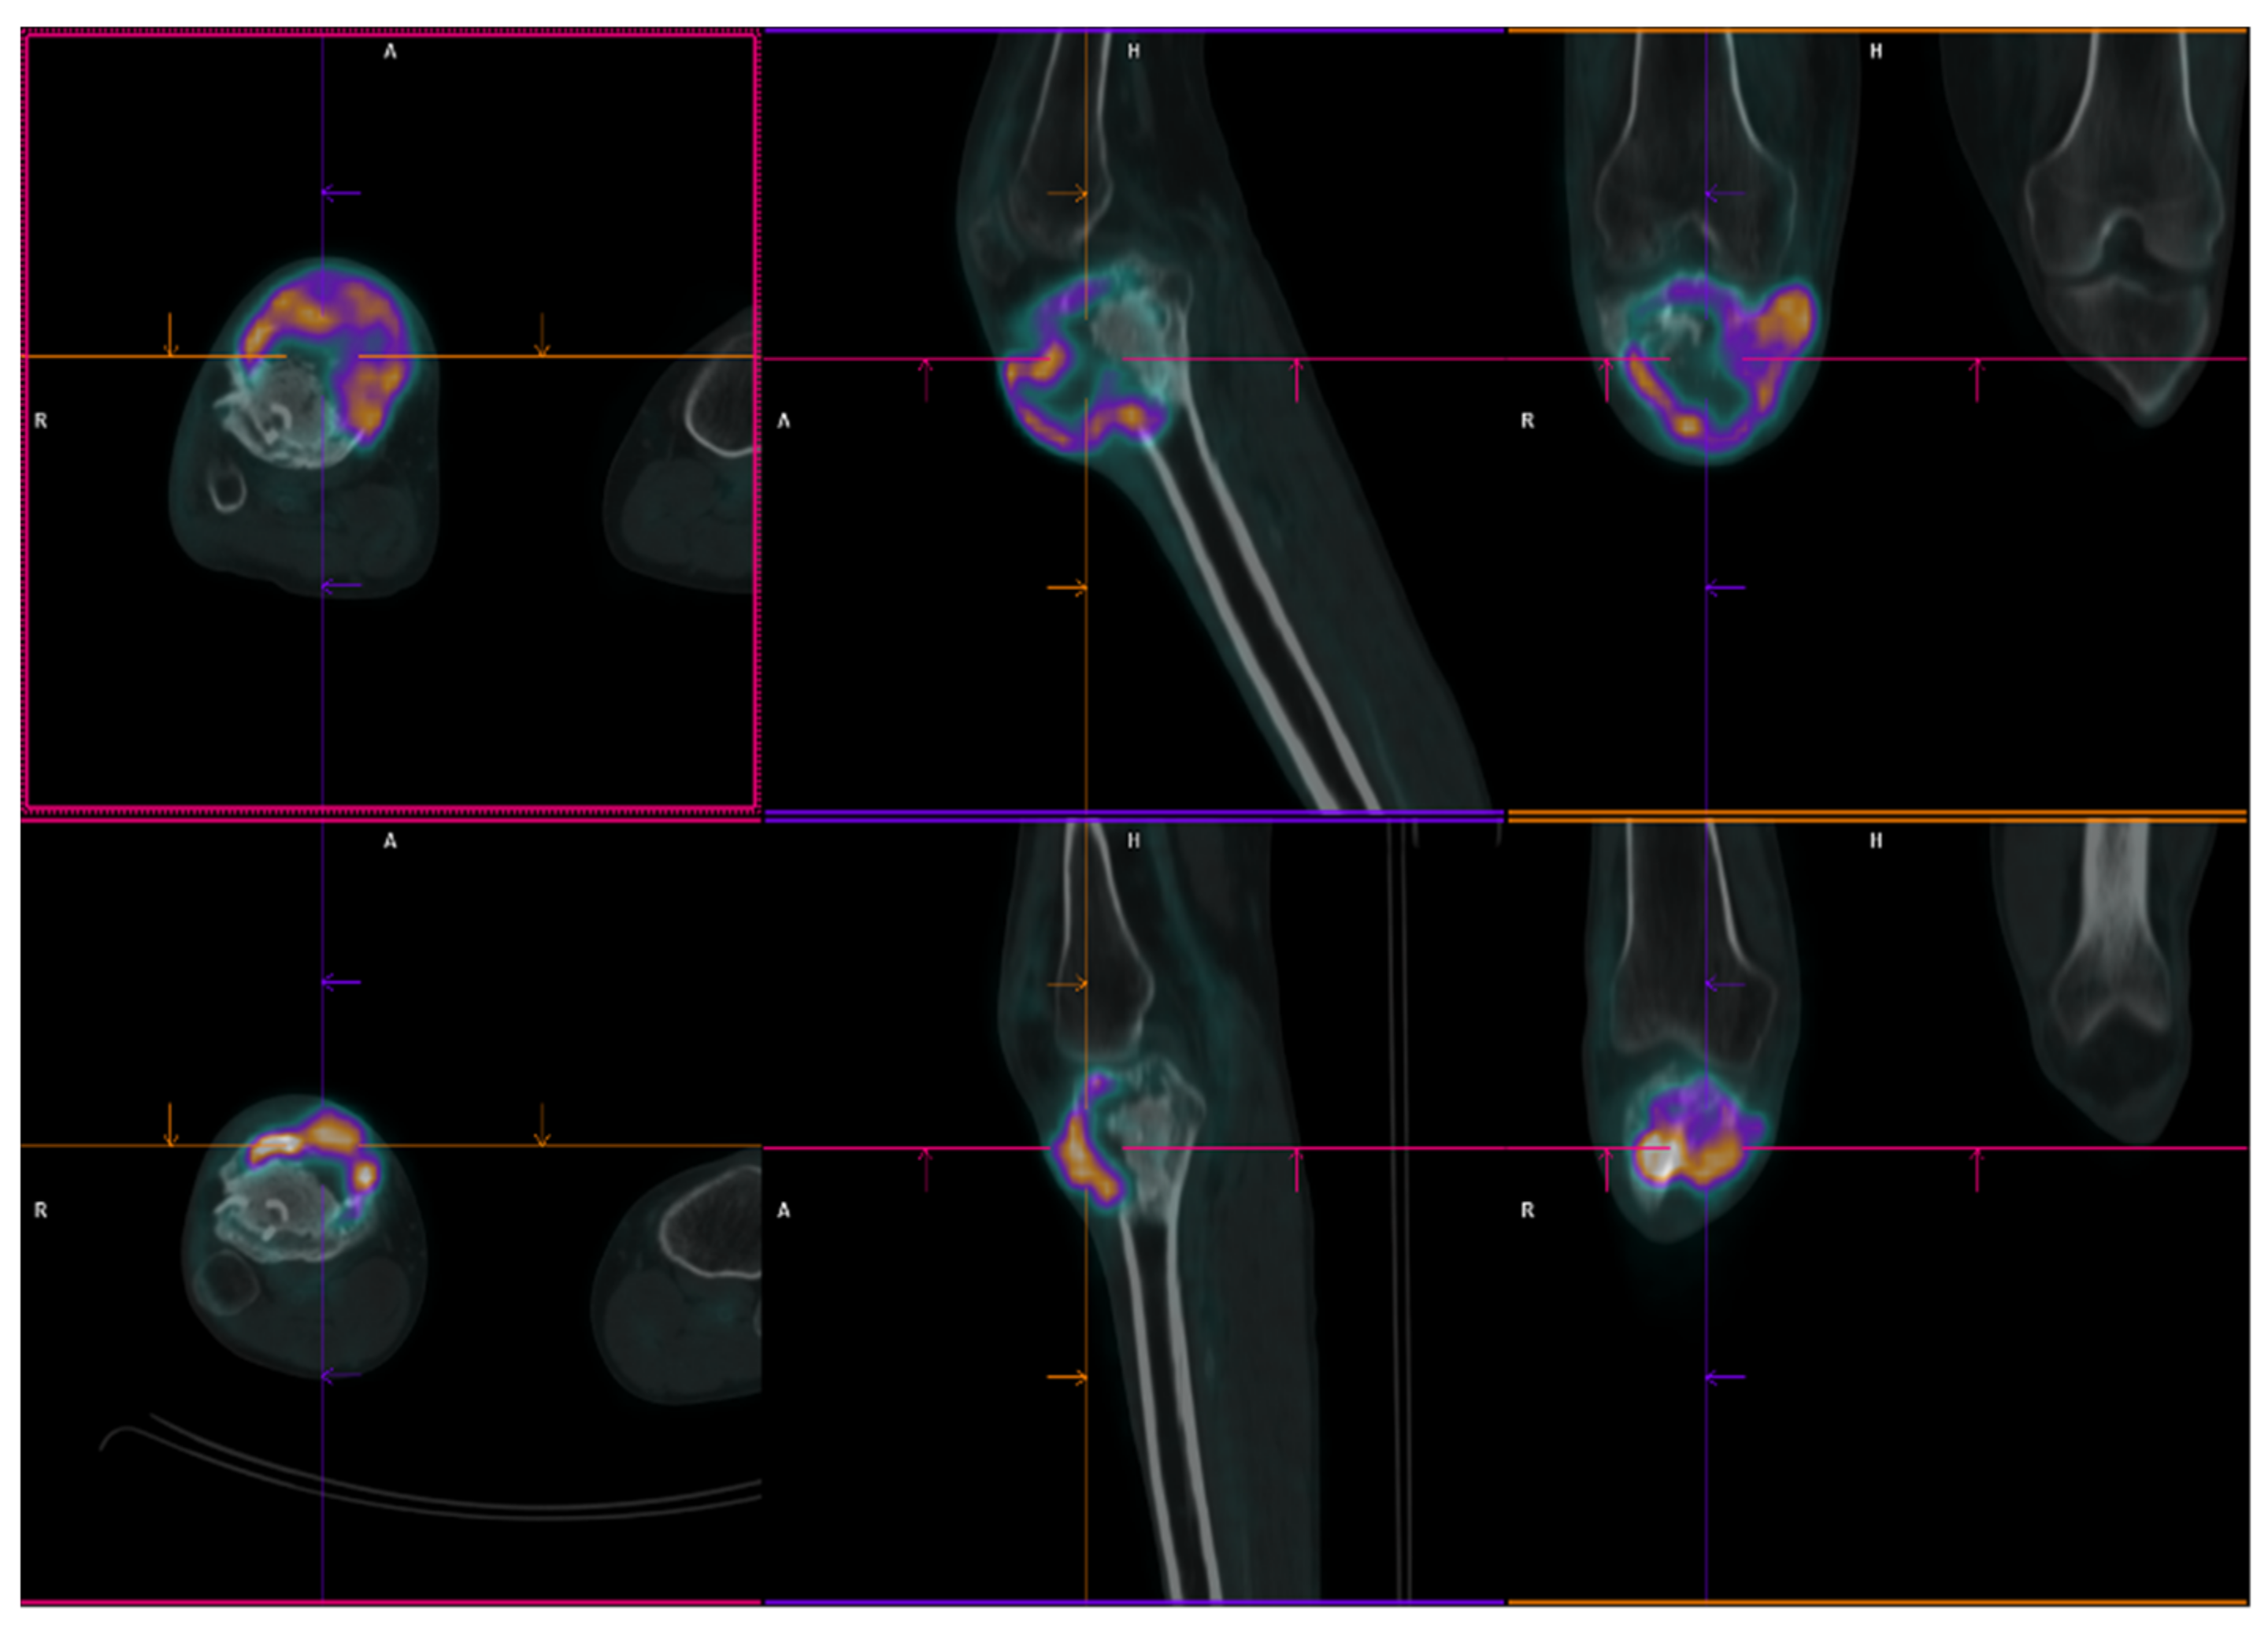

2.1. Patient 1

2.2. Patient 2

2.3. Patient 3

| Age | Sex | ECOG PS | Diagnosis (Date) | Site of Primary GCTB | Surgery | Rec. Date | Treat. Management | Malignant Transformation (Date/Surgery or Biopsy) | Treat. | Evolution | Subsequent CHT Lines | FU/D | Time to MT (Months) | OS from GCTB Diagnosis (Months) | OS from MT (Months) | |

|---|---|---|---|---|---|---|---|---|---|---|---|---|---|---|---|---|

| Pt 1 | 29 | F | 0 | 17 July | Right femur | Curettage and bone grafts | 18 February | Neoadj denosumab (7 cycles) | 18 July Extraarticular resection: high-grade fibroblastic osteosarcoma | ISG/OS-2 | PD | I: IFO II: GEM.TXT III: PAZO | D 22 January | 9 | 53 | 43 |

| Pt 2 | 48 | M | 0 | 16 November | Right tibia | Curettage and bone grafts | 20 October | Neoadj denosumab (6 cycles) | 21 February Extraarticular resection: malignant transformation of GCTB | EURO BOSS | NED | - | FU 21 December | 51 | 64 | 13 |

| Pt 3 | 20 | F | 0 | 10 September | Left femur | Resection of the femoral head, curettage and bone grafts | 11 March | Biopsy | 11 June Biopsy: high-grade osteosarcoma G3 with aberrant expression of beta-HCG | ISG/OS-1 | PD | - | D 11 November | 9 | 14 | 5 |